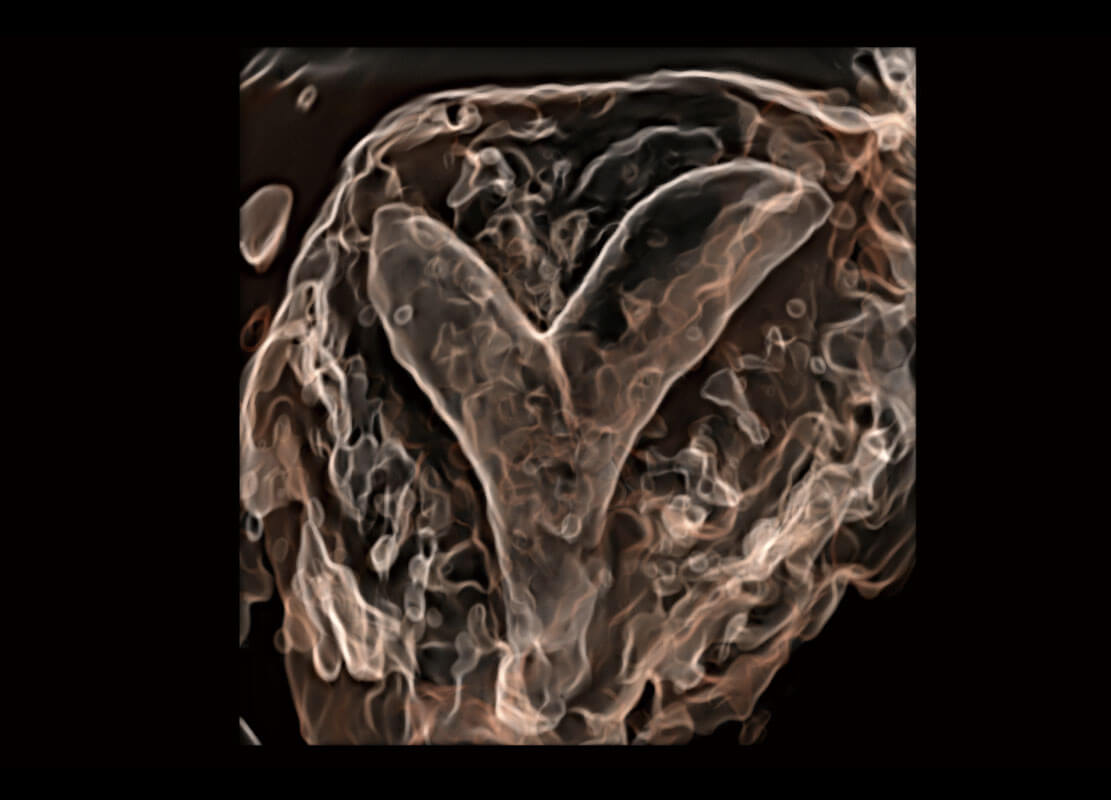

腔內(nèi)三維-光影成像

光影成像-孕囊